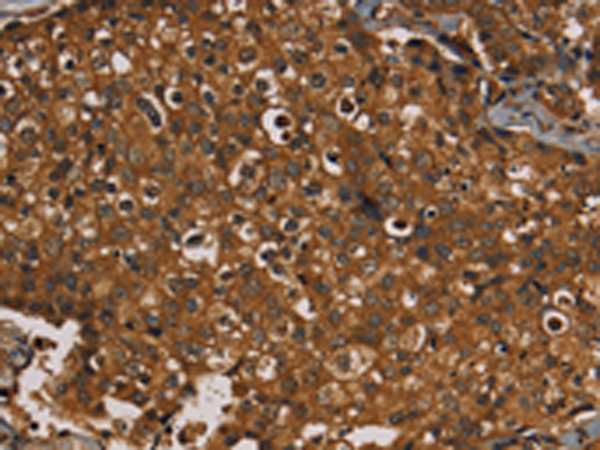

分类: 科研抗体货号: P08427别名: IDH; IDP; IDHM; IDPM; ICD-M; D2HGA2; mNADP-IDH应用: WB,IHC反应种属: Human, Mouse, Rat